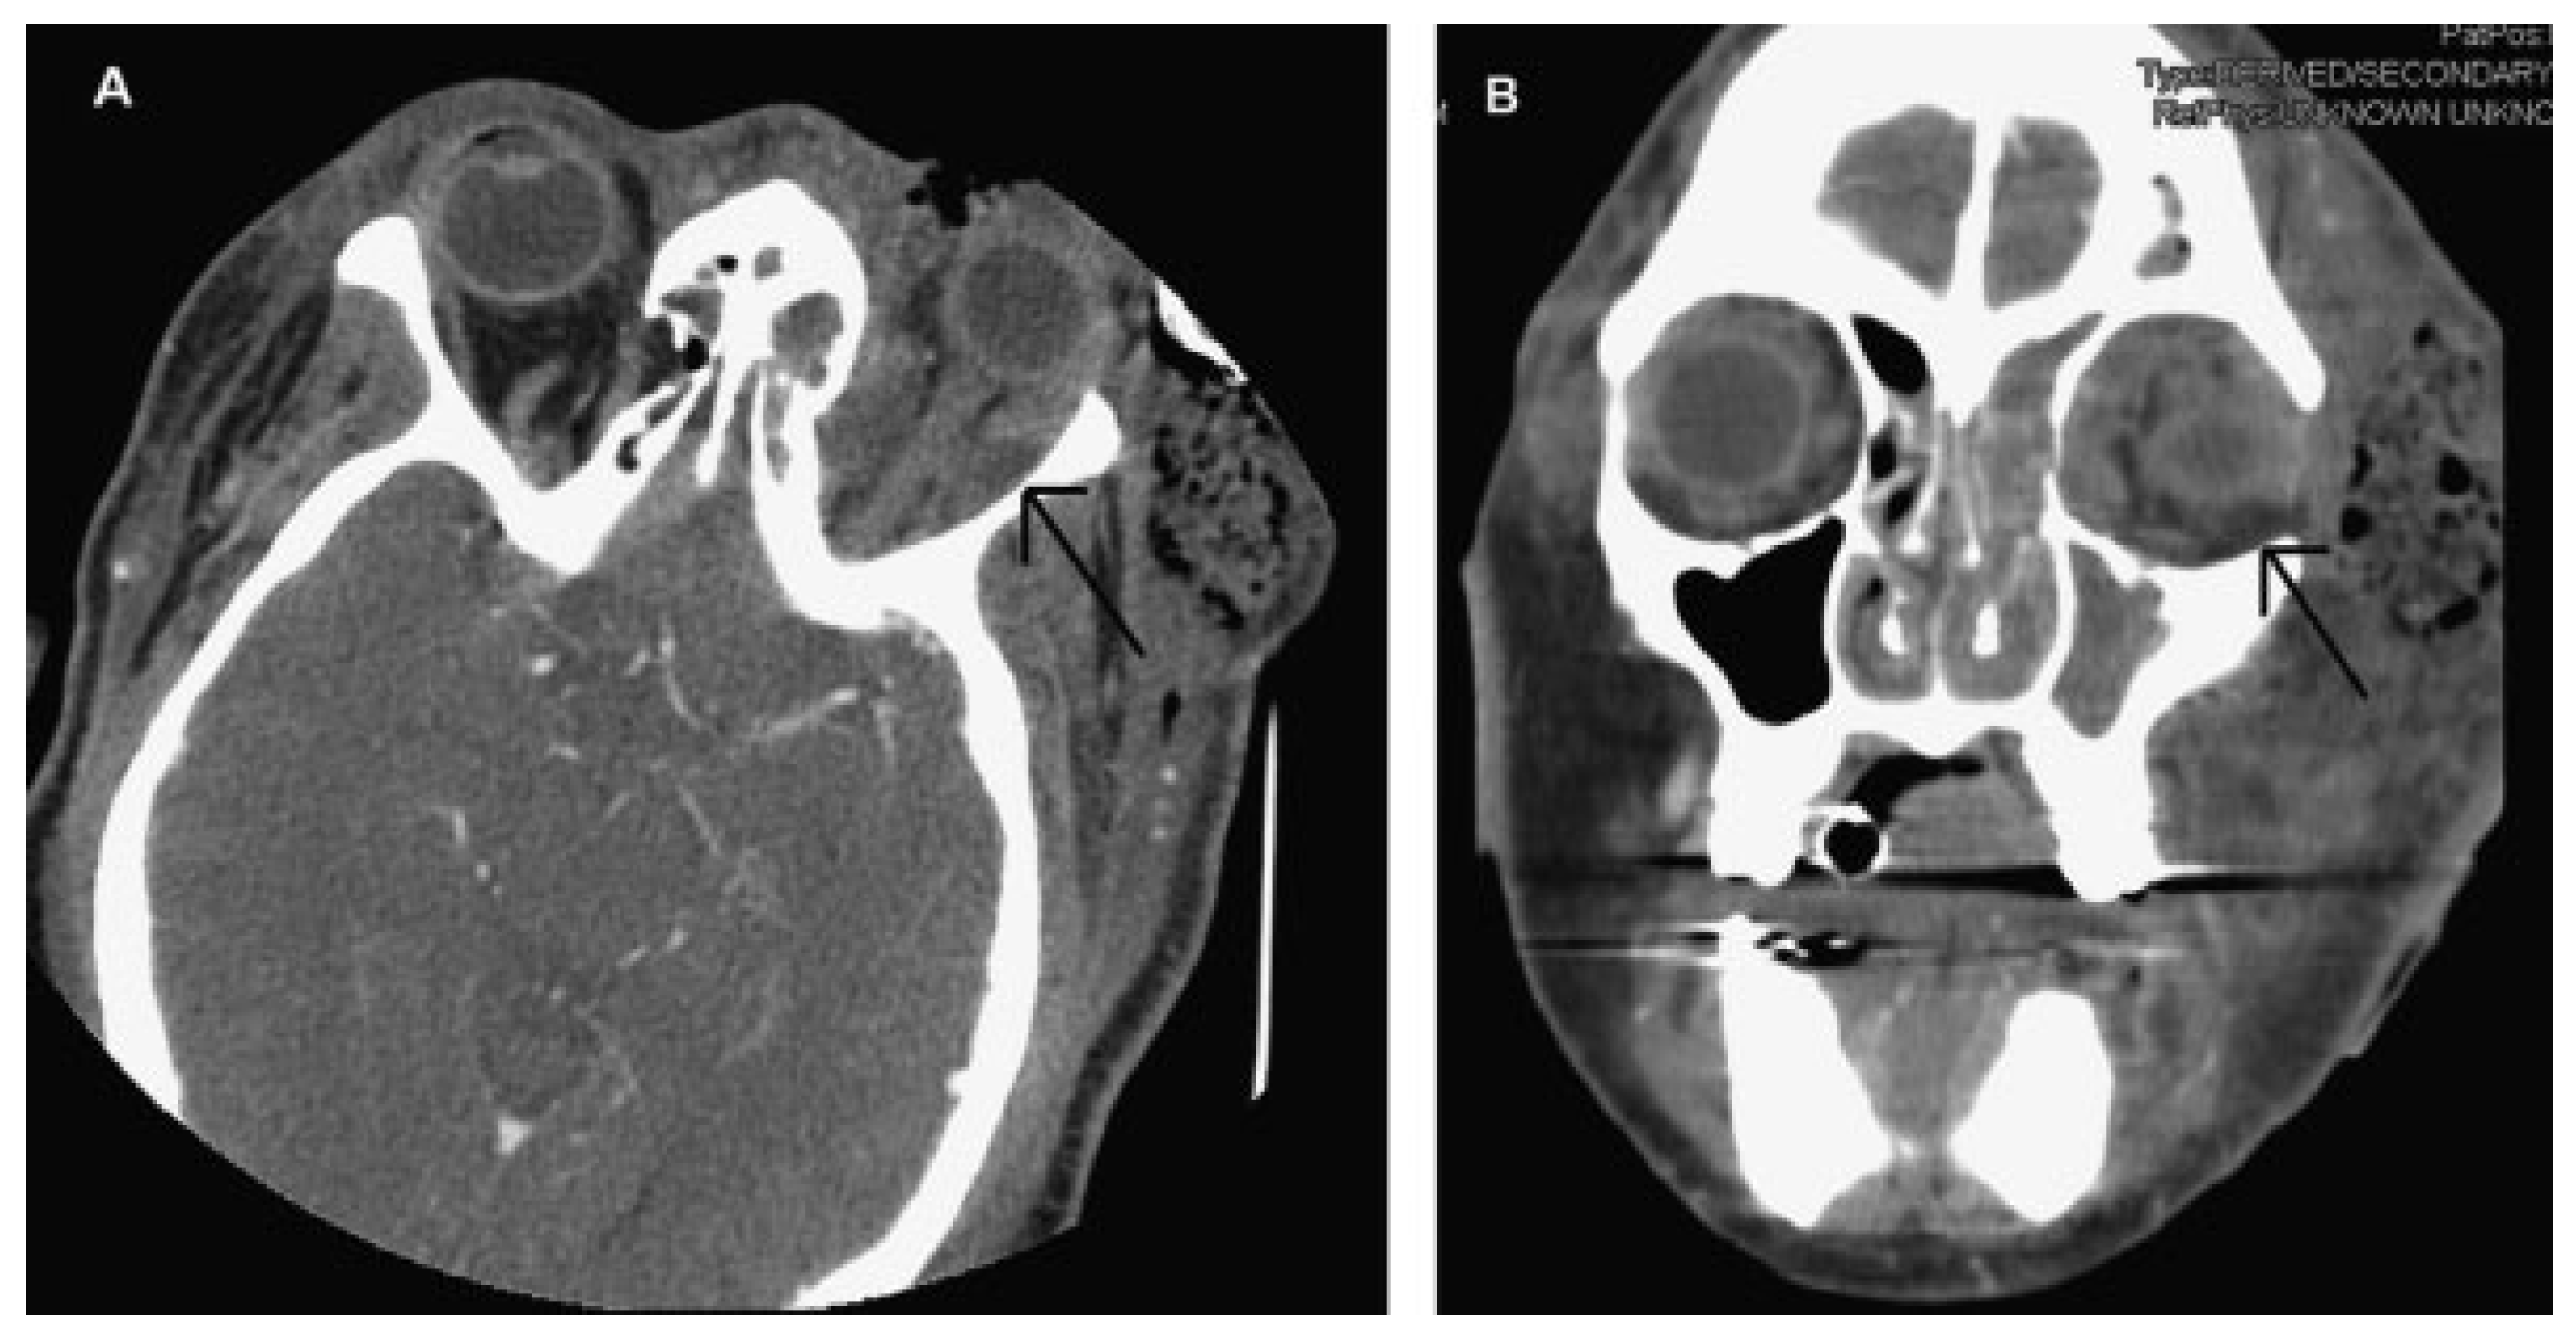

The patient was taken immediately to the operating room due to her worsening clinical presentation and the authors’ suspicion for necrotizing soft tissue infection. Incision and drainage and debridement of the necrotic tissue were performed on the left periorbital, zygomatic, and temporal regions (►Figure 3A–D). Copious purulent drainage was obtained which was submitted for Gram stain and cultures. Irrigation of the wound was then performed until no further murky fluid was appreciated with approximately 5 L of 0.9% normal saline. The wound was then packed in a standard wetto-dry fashion. The patient was placed on vancomycin, piper-acillin/tazobactam, and metronidazole and transferred to the intensive care unit (ICU) where she remained intubated and sedated. In the ICU, she was supported medically, including optimization of her blood glucose. Overnight, the patient remained tachycardic and febrile with a maximum temperature of 103°F (39.4 °C). At that time, a maxillofacial CT with contrast was obtained, which revealed left periorbital, orbital, and buccal inflammatory changes. Proptosis, lateral and downward displacement of the globe, and homogeneous opacification of the frontal, ethmoid, and maxillary sinuses were appreciated on the left side. The right ethmoid sinus was partially opacified, which justified the inflammatory changes in the right orbit. Additionally, a large fluid loculation of the left lateral pharyngeal space was present (►Figure 4). The intraoral examination revealed a large localized swelling of the left oropharynx and nasopharynx, with deviation of the palatal uvula from the midline. Ophthalmology was reconsulted. On postoperative day 2, the patient was taken back to the operating room for incision and drainage of the left maxillary sinus and left lateral pharyngeal space and washout of existing wound. An intraoral incision was made on the left posterior oropharynx and blunt dissection was performed to enter the left lateral pharyngeal space where approximately 15 mL of purulence was obtained and samples were sent for cultures and sensitivities. Three nonrestorable, grossly carious left maxillary posterior teeth were then extracted to negate any possible source of odontogenic infection; however, no purulence or periapical involvement of the teeth was evident upon extraction. This made an odontogenic cause of the infection unlikely. The left maxillary sinus was entered via a standard Caldwell-Luc approach to drain the fluid collection appreciated on CT and an additional 5 to 10 mL of purulence was obtained. After copious irrigation of the sites, two ½ inch Penrose drains were placed, one in the left maxillary sinus and the other in the left lateral pharyngeal space. The drains were then secured to the oral mucosa with sutures. Washout and redressing of the left periorbital wound was then performed and the patient returned to the ICU intubated. Laboratory values showed white blood cell count of 15.9 g/dL, hemoglobin of 12 g/dL, hematocrit of 36.4%, and platelet count of 226,000/µL. Chemistry showed sodium level of 134 mmol/L, potassium level of 3.5 mmol/L, chloride level of 97 mmol/L, bicarbonate level of 27 mmol/L, blood urea nitrogen level of 6 mg/dL, creatinine level of 0.7 mg/dL, and glucose level of 375 mg/dL. Hemoglobin A1C was 12.8 and C-reactive protein was 34.2 mg/dL. The patient’s previously recorded hemoglobin A1C was 13.0 recorded 26 months earlier at the medicine clinic showing long-term poor diabetic control. Over the next few days, the patient clinically improved and her vital signs stabilized with the exception of a persistent elevated temperature of 101°F. Cultures came back as group C β hemolytic Steptococcus and Proteus mirabilis. After consultation with the infectious disease service, the antibiotics were narrowed to ampicillin/sulbactam and clindamycin. A repeat CT scan was obtained on hospital day 5 and a loculation was noted at the superior and lateral aspect of the left orbit, suggestive of subperiosteal abscess (►Figure 5A,B). Ophthalmology service recommended no intervention for the left orbital subperiosteal abscess. However, as the patient was still having low-grade temperature of 101°F (38.3 °C), the authors took the patient back to the operating room for incision and drainage of this area. We approached the superior-lateral orbit via an existing incision, and approximately 5 mL of purulence was obtained. Postoperatively, the patient improved clinically, and became afebrile. The intraoral drains were removed, and after cons ultation with the wound nurse, the wet-to-dry dressing of the skin was changed to petroleum-impregnated gauze. Despite our objection, the patient remained intubated for a prolonged period due to the discomfort of the ICU team in extubating the patient. The patient was extubated on hospital day 12. On the day of discharge, examination revealed significant decrease in left periorbital swelling, decrease proptosis, and increase extraocular movement in all directions; however, she continued to have 20/400 vision in the left eye and diplopia. Due to the defect in the left upper and lower eyelids, a home care nurse was assigned for daily dressing changes. Intraoral examination demonstrated resolution of swelling of the oropharynx. A maxillofacial CT scan revealed resolution of the original fluid loculations and a patent airway. Throughout the postoperative hospital stay, the patient’s glucose level and blood pressure were controlled. The patient was discharged on hospital day 13 with oral antibiotics, amoxicillin/clavulanic acid, and clindamycin, as well as her home antihypertensive and diabetic medications. The patient was closely followed up and her condition continued to improve. At 4 months follow-up, the patient presented with resolution of facial swelling; had proptosis and eyelid ptosis, normal extraocular movements; and her baseline visual acuity of her left eye remained 20/400. The patient was seen 1 year postoperatively and had continued resolution of her wounds with appropriate wound closure; however, she had continued strabismus, ptosis of the upper and lower lid secondary to scar contraction, as well as left V2 paresthesia (►Figure 6A,B). The orbital wound continued to heal via secondary intention with anticipated reconstruction and scar revision in the near future.

Figure 4. Axial computed tomographic scan showing the involvement of the left lateral pharyngeal space. Arrow shows well loculated abscess in the lateral pharyngeal space.